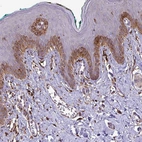

Immunohistochemistry analysis in human epididymis and skeletal muscle tissues using HPA016997 antibody. Corresponding P4HA2 RNA-seq data are presented for the same tissues.